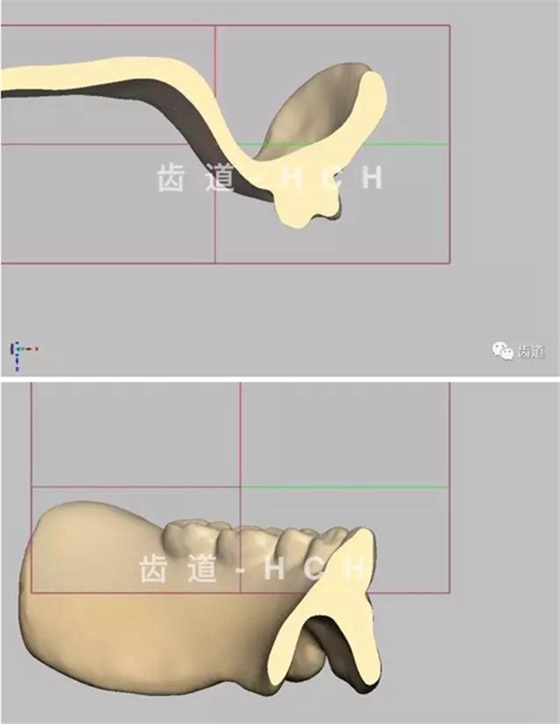

標(biāo)準(zhǔn)全口義齒模型截圖 科貿(mào)嘉友收錄